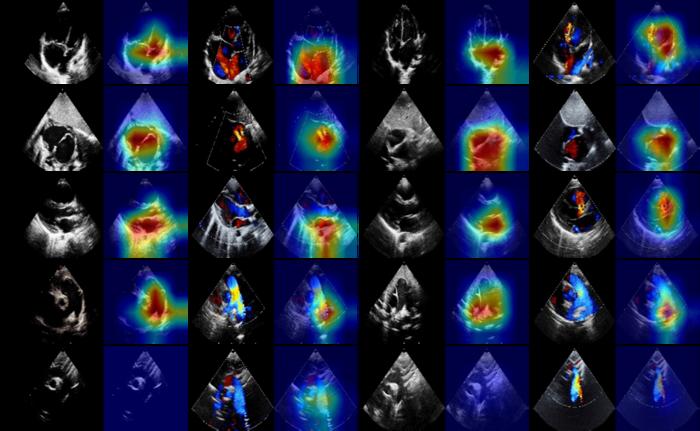

The team met the challenge by creating a hierarchical network structure. The model first recognized the two modalities (2D and Doppler TTE) and identified the cardiac views of TTEs: apical four chamber (A4C), subxiphoid long axis view (SXLAX) of two atria, parasternal long-axis view (PSLAX) of the left ventricle, parasternal short-axis view (PSSAX) of aorta, and suprasternal long-axis view (SSLAX). Then, the model embedded the features per view for each modality based on the backbone network ResNet50. After the basic feature embedding module, the model fused the embeddings of five views and then merged the information from two modal TTEs. Finally, the prediction of each subject was calculated from the classifier, and the visualization of high-risk regions for each child was generated using the Grad-CAM strategy.

After the child completed the TTE examination, Xie’s auxiliary CHD diagnostic system automatically analyzed the TTE images and computed the probability of each subject being normal, having ASD, or having VSD. The researchers demonstrated that the model accurately identified the children with CHD by integrating the TTEs with multiple views and modalities. The results suggested that the model has the potential to facilitate and improve widespread screening and the distinguishing of CHD subtypes in children.